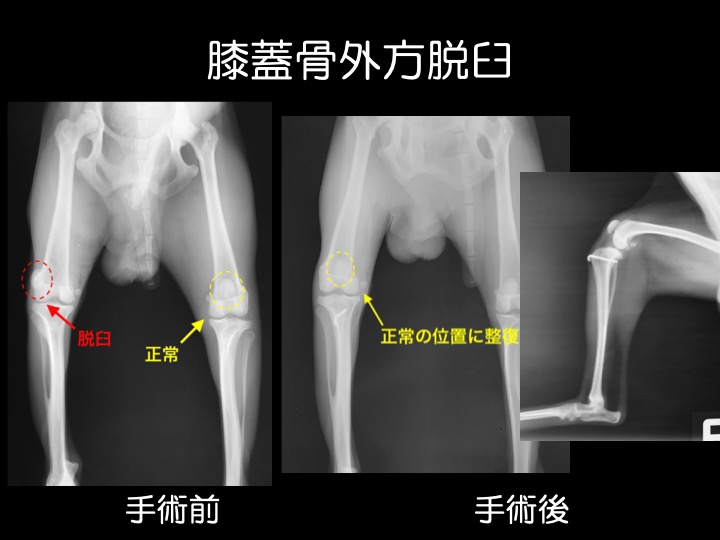

・内方脱臼と同様に外傷が原因で脱臼することもありますが、多くは先天性で成長期の異常として見つかります。中等症以上の場合には、手術が検討されます。

・写真のワンちゃんのように、経過が長い子は、痛みから足を着かなくなってしまい、足全体の筋肉が徐々に痩せていってしまいます。

・外方脱臼は内方脱臼よりも痛みが強く出る傾向があり、跛行などの症状も顕著です。

※ 大型犬に見られる外方脱臼は、小型犬のそれとは異なる病態と考えられており、治療にあたっては専門的な知識や経験が必要です。高度医療施設への受診を推奨しています。